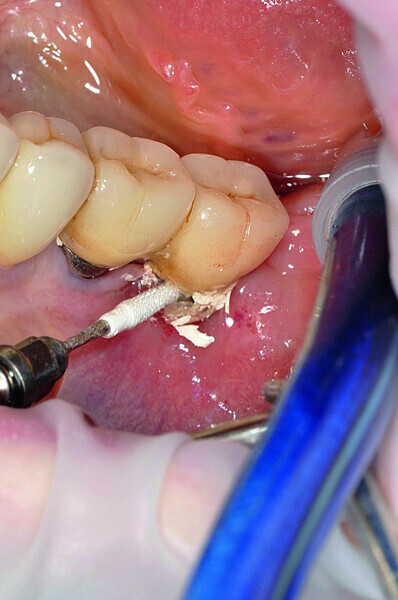

Fig. 5a: Professional peri-implant biofilm removal by a) AIRFLOW with erythritol powder (PLUS powder, EMS), b) PERIOFLOW with PLUS powder and c) with PEEK tip (PI, EMS).

Fig. 5b: Professional peri-implant biofilm removal by a) AIRFLOW with erythritol powder (PLUS powder, EMS), b) PERIOFLOW with PLUS powder and c) with PEEK tip (PI, EMS).

Fig. 5c: Professional peri-implant biofilm removal by a) AIRFLOW with erythritol powder (PLUS powder, EMS), b) PERIOFLOW with PLUS powder and c) with PEEK tip (PI, EMS).